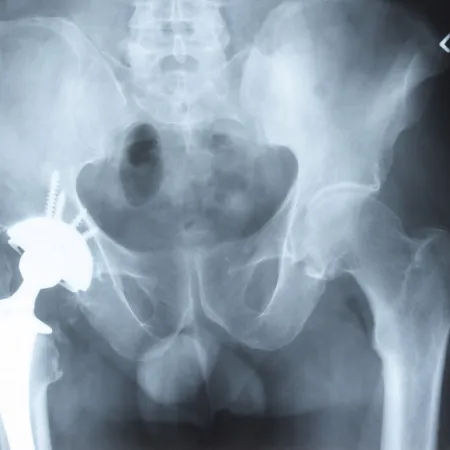

ข้อสะโพกเทียมไม่แท้แต่แก้ได้ ข้อสะโพกเป็นรอยต่อระหว่ากระดูกเชิงกรานกับกระดูกต้นขา ประกอบไปด้วย 2 ส่วนสำคัญ ได้แก่ ส่วนที่เป็นหัวกระดูกสะโพกมีรูปร่างก...